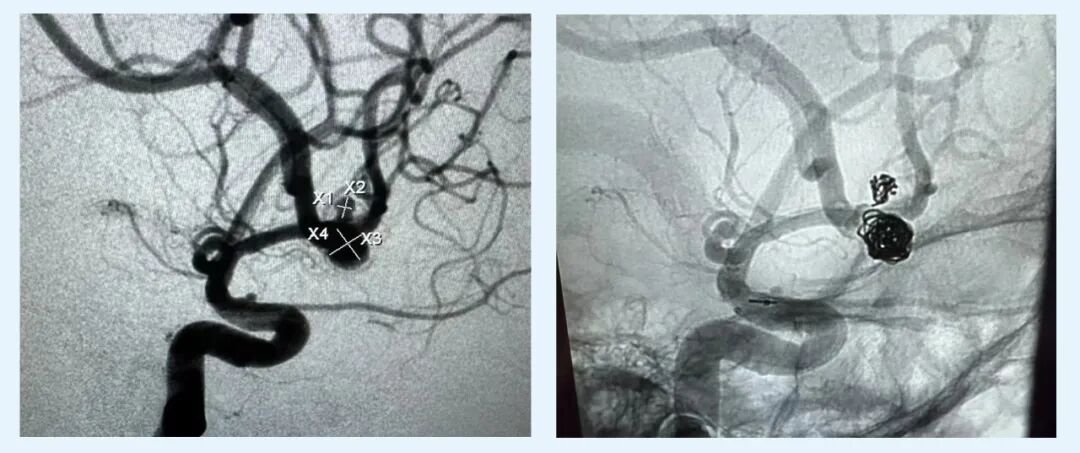

家人緊急將其送醫(yī)救治,經頭部CT診斷顯示為頸內動多個脈瘤破裂伴蛛網膜下腔出血,此外,因為發(fā)病時嘔吐及意識喪失,嘔吐物經由氣道進入了肺部,導致了吸入性肺炎。

診斷結果出來后,惠州市第三人民醫(yī)院(以下簡稱“惠州三院”)神經外科的醫(yī)生當即為張姨進行了介入栓塞手術,手術順利完成,張姨暫時脫離了生命之危。